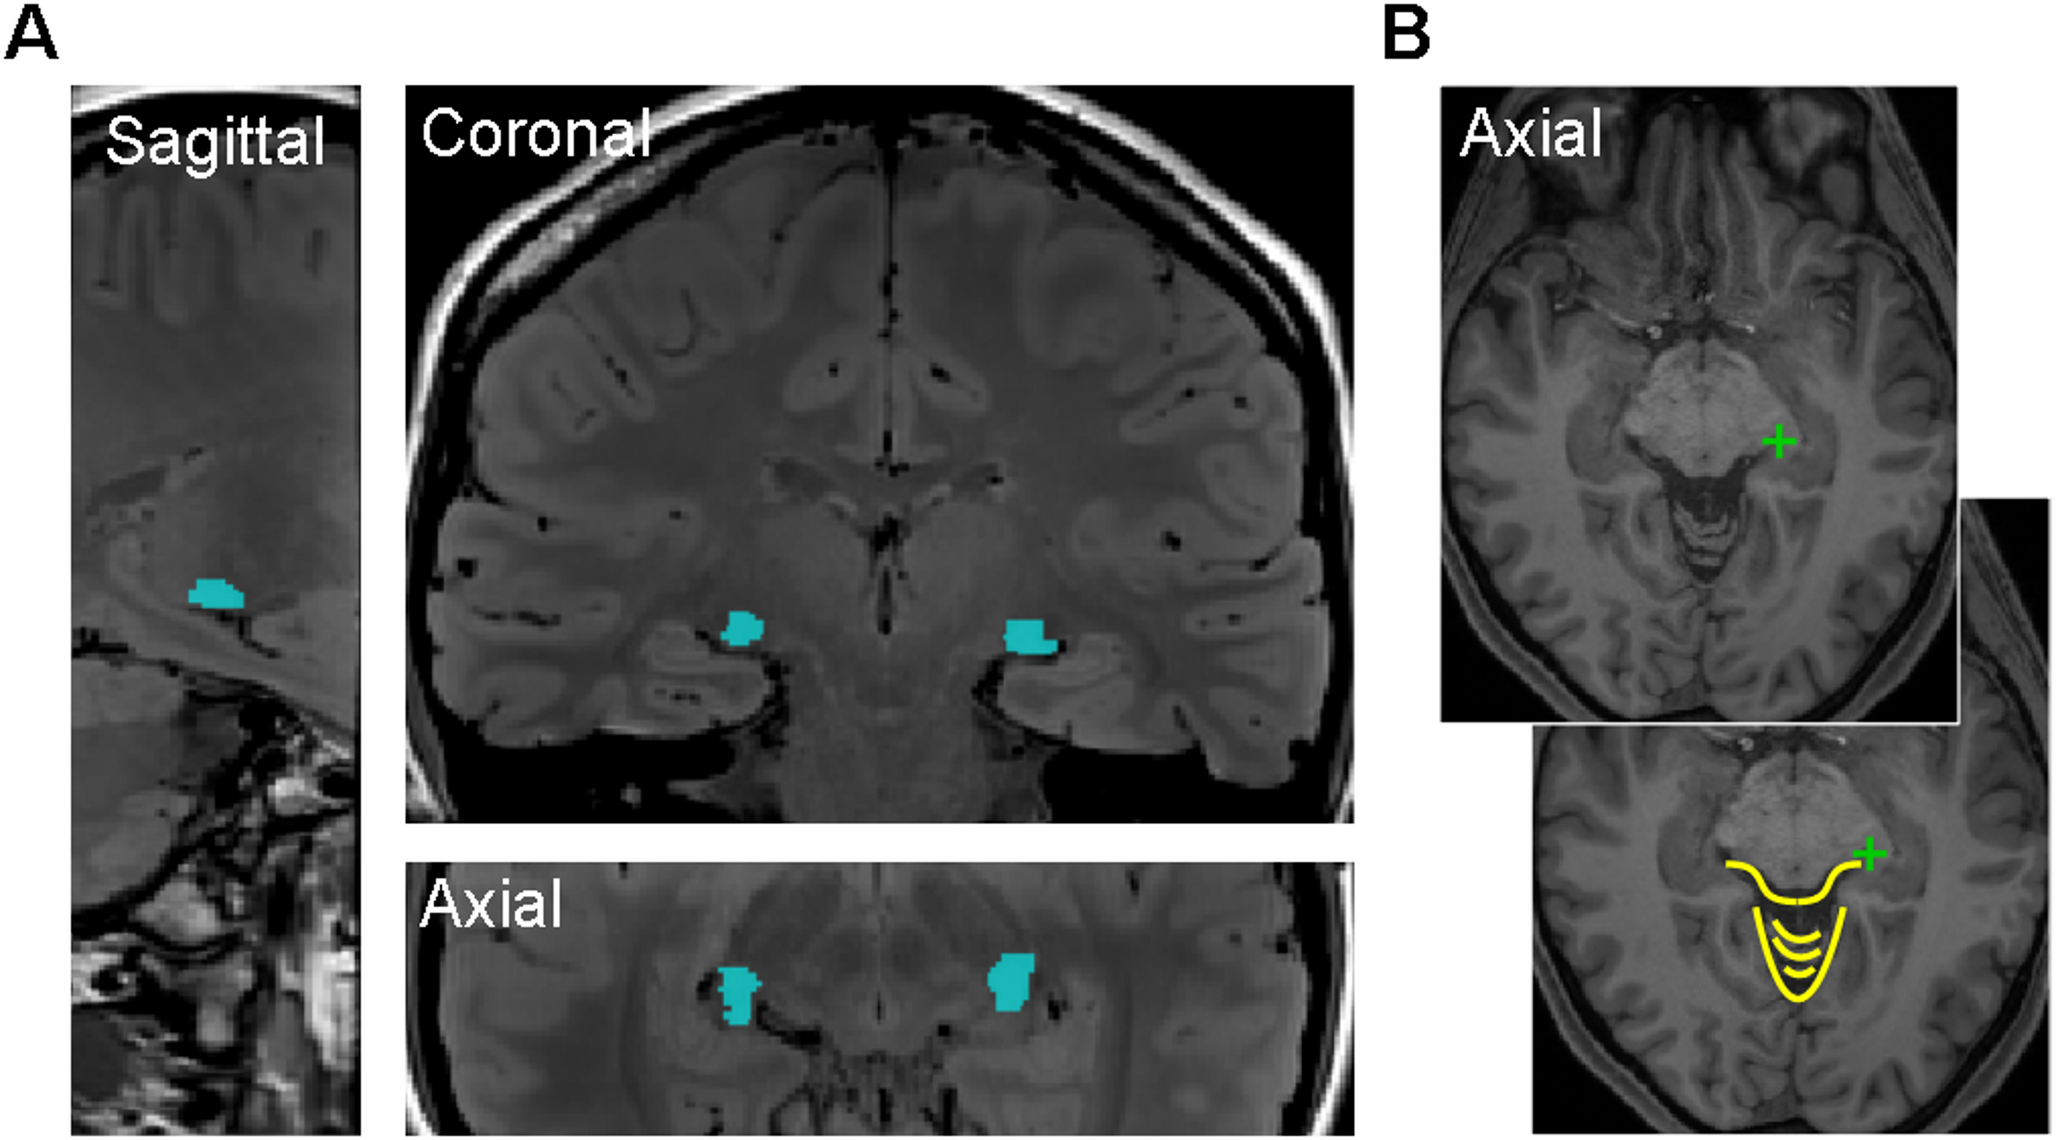

Evaluating the effective segmentation of human lateral geniculate nucleus

Important parts of the visual pathway occur in relatively small subcortical structures that are often difficult to identif...